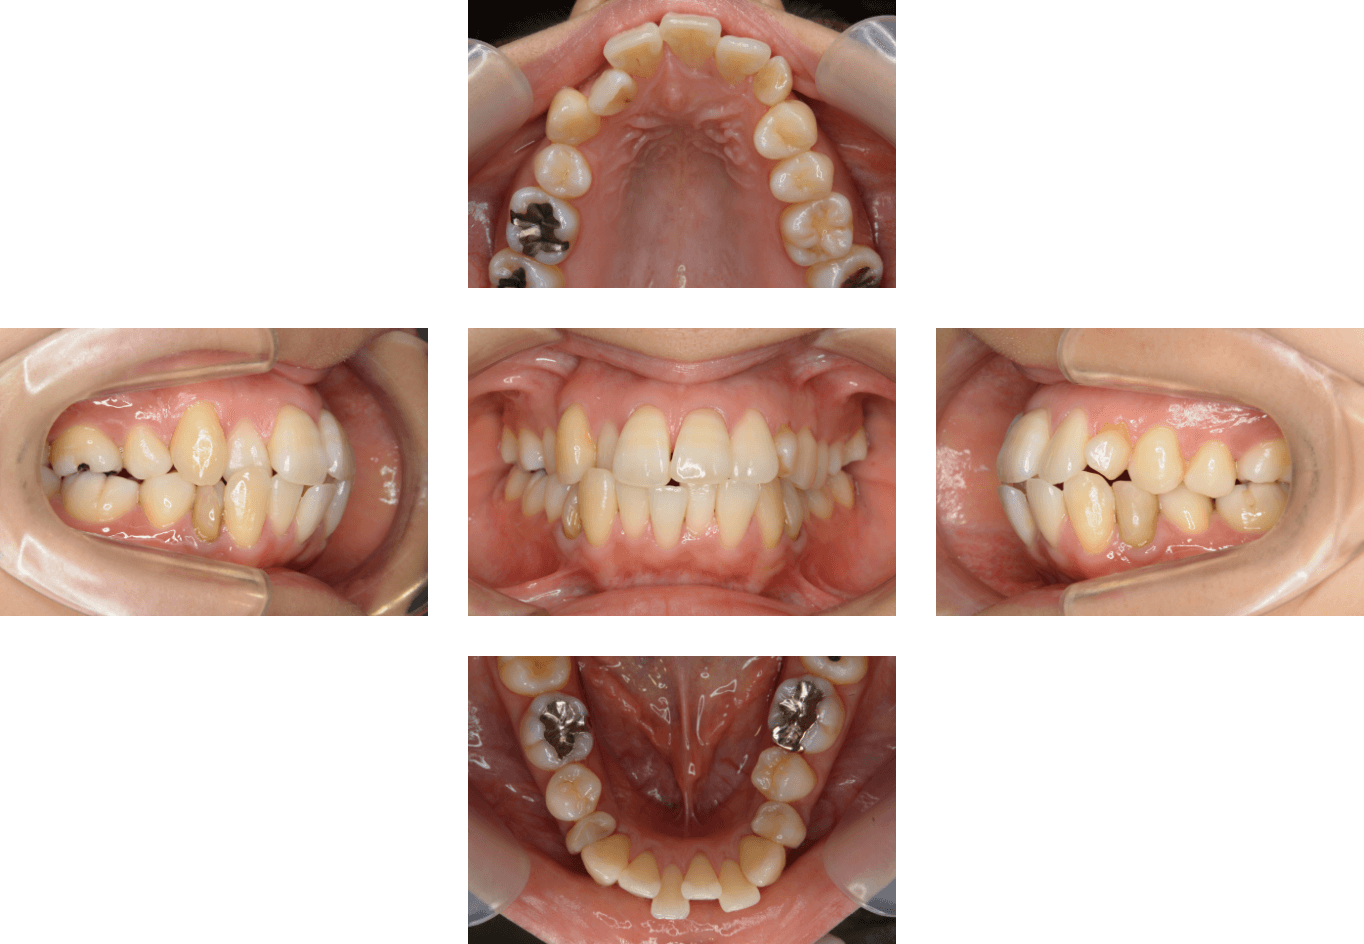

Case3

| 主訴 | 歯が埋まっている、歯が足りない |

|---|---|

| 診断名 | 上顎左右4番の欠損、左上E晩期残存、左上5番の埋伏歯 |

| 年齢 | 22歳11ヶ月 |

| 治療に 用いた装置 |

リンガルブラケット矯正装置(エッグブラケット)、 マルチブラケット装置 |

| 抜歯部位 | 右下5番 |

| 治療期間 | 2年6ヶ月 |

| 治療費用 | 1,160,500円 |